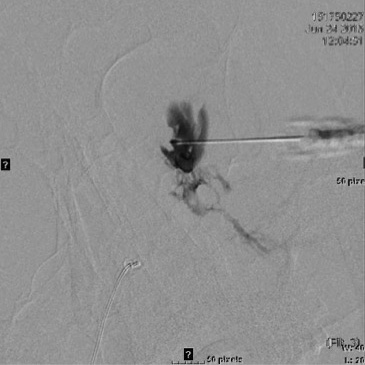

Once safely accessed, aspiration of lymph or blood will confirm needle or catheter position. When treating a large LM cyst with a catheter, the lesion is completely aspirated, a small contrast cystogram is performed to exclude cyst rupture, and then sclerosant(s) are injected and allowed to dwell in the cyst for a short time before complete aspiration. In our practice, these cysts are treated with a small amount of STS for 5 minutes followed by Ethanol for 15-20 minutes. We keep the catheter to bulb suction for 48 hours prior to removal, as very caustic agents will stimulate fluid generation. Lacking a catheter for decompression this can lead to significant swelling behind the globe.

MRI of large LM cyst (top), catheter passing through lower lid (left), cystogram (right).

If treating a VM, as in treating a VM anywhere else in the body, a venogram under fluoroscopy is useful to assess the size of the lesion, the routes of venous drainage, and the rate of run off. Using standard fluoroscopic guided sclerosant injection techniques, the foams are all very well visualized especially under subtraction technique.